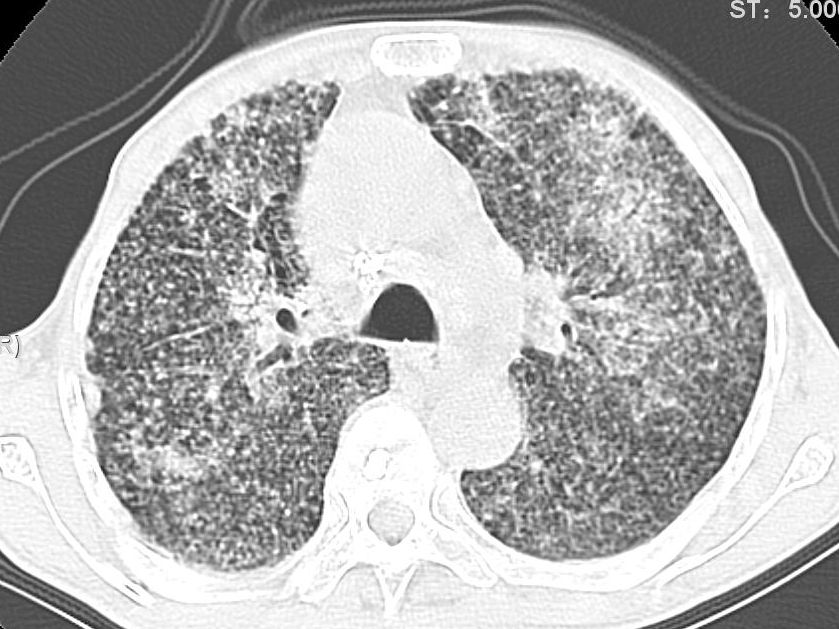

患者咳嗽月余,高热数天,咳黄色稍脓痰。

双肺野分布多个小结节状高密度影,其内散在斑片状模糊影,气管。支气管通畅,纵隔内淋巴结钙化,胸膜局限性增厚粘连,胸腔少量积液。结合病史考虑结核并感染的可能性大,胸膜炎并积液。肺泡癌待排。

纵隔内见钙化的淋巴节,上肺见钙化灶,双肺均匀弥漫分布小结节影,边缘较清楚,能不能考虑是在矽肺的基础上并发的结核和感染,请详细了解病史结合临床.